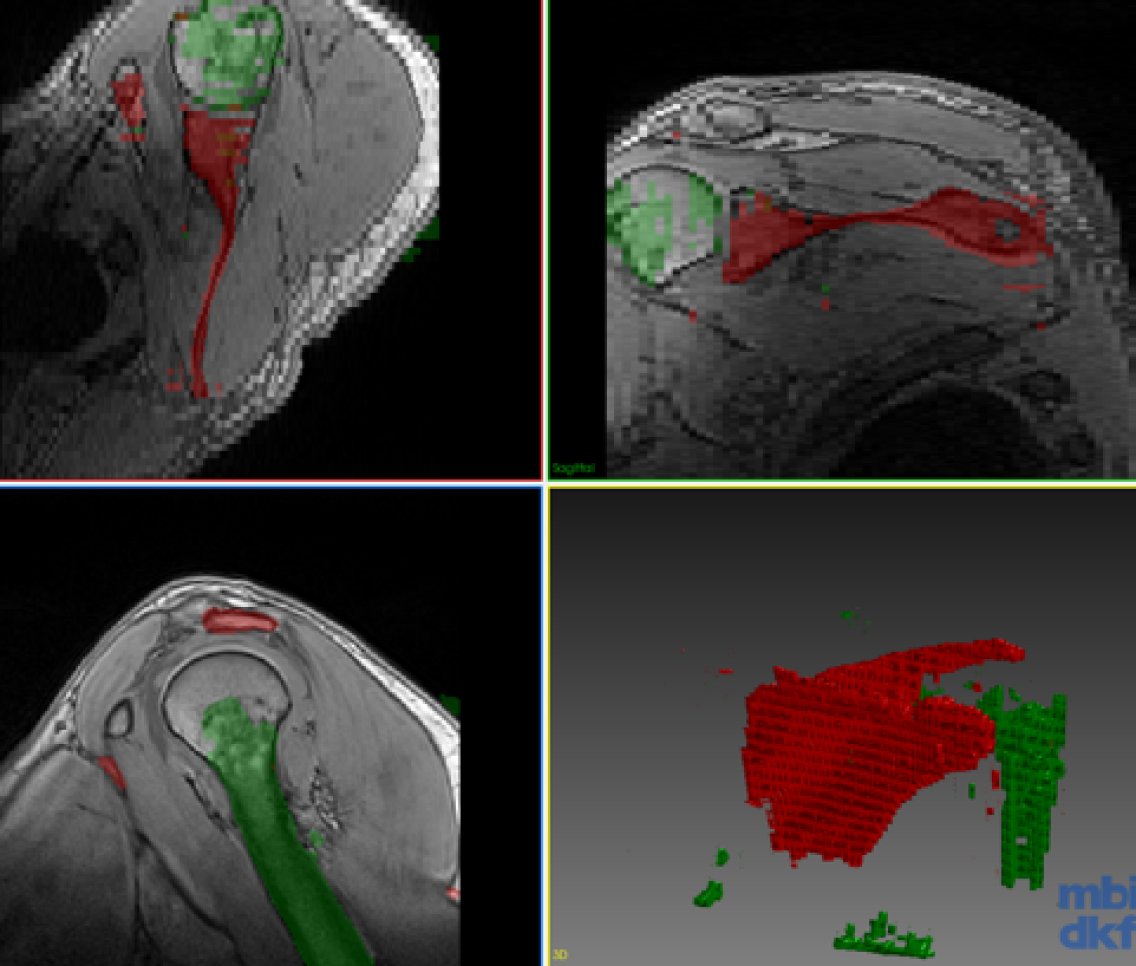

Refer to caption

(a) Gold Standard

(b) CoRiSeg Case 1

Figure 3: Segmentation of the test volume with different methods.

Our experimental dataset consists of 9 Dixon sequences of left shoulder collected with 1.5 Tesla at resolution of 0.91 mm x 0.91 mm x 3 mm, corresponding to 192x192x64 voxel resolution. Humerus and scapula bones were annotated by an expert. Our goal is to combine knowledge from different data for a network that can segment both anatomical structures. We evaluated our proposed method for the three scenarios shown in the table in Fig. 2. One volume each was fixed randomly for validation and testing each of all scenarios. The first scenario (Case 1) tests a typical setting where different anatomies were of interest and thus annotated in separate studies. The second scenario (Case 2) aims to observe advantages of incremental training with minimal effort, i.e., incrementally annotated data, giving insight on an extreme case where a single volume annotation is provided. The last scenario (Case 3) studies the feasibility of combining learned segmentation information from different anatomy and images of different contrast. The methods were implemented with Tensorflow [14] and ran on an Nvidia Titan X GPU. Proposed network is implemented in 2D, hence 646464 image samples per volume given in Fig. 2. For a fair comparison, we fixed all parameters across different models to kcsubscript𝑘𝑐k_{c}==505050, krsubscript𝑘𝑟k_{r}==303030, α𝛼\alpha==0.50.50.5, tMCsubscript𝑡MCt_{\mathrm{MC}}==292929, batch size of 8 images, and trained all models for 1000 epochs. Used network (cf. Fig.1) has a first convolutional layer with 64 filters and the amount of filters double at every coarsening level. Each convolutional layer is proceeded with a batch normalization and ReLU activation. For CoRiSeg, we use a VGG16 network [7] pre-trained on ImageNet [13]. While a VGG trained on a medical image set would be expected to provide more accurate dcontsubscript𝑑contd_{\mathrm{cont}} score, training set of ImageNet is not matchable by any annotated medical database. We used Dice similarity coefficient and average symmetric surface distance for evaluating segmentation performance across tested methods (cf. Table 1). We compared our proposed methods: LwfSeg with its extensions with exemplar sets AeiSeg and CoRiSeg. Upper bound cases are presented with networks trained on only a given anatomy/dataset, i.e., without any incremental learning and hence without the need to preserve “old” (extra) information. We also show results from finetuning for comparison, although catastrophic forgetting is a known problem. In Fig. 3, we showcase qualitative results from different scenarios (cf. table in Fig. 2).

Note the high average symmetric surface distance in some of the proposed incremental methods, i.e., AeiSeg and CoRiSeg in Case 2; LwfSeg in Case 3. These are due to small blobs of false positives far from the target anatomy (cf. Fig. 3). These blobs could possibly be removed with a trivial post processing step (e.g. morphological operations, largest connected region, conditional random fields, user input), which is beyond the objective of this paper. Additional randomized hold-out test sets for Case 3 showed little variation (\approx2% Dice) in results, while the proposed AeiSeg and CoRiSeg were still over 27% Dice better than LwfSeg in retaining old class info. We will conduct extensive evaluations in future.